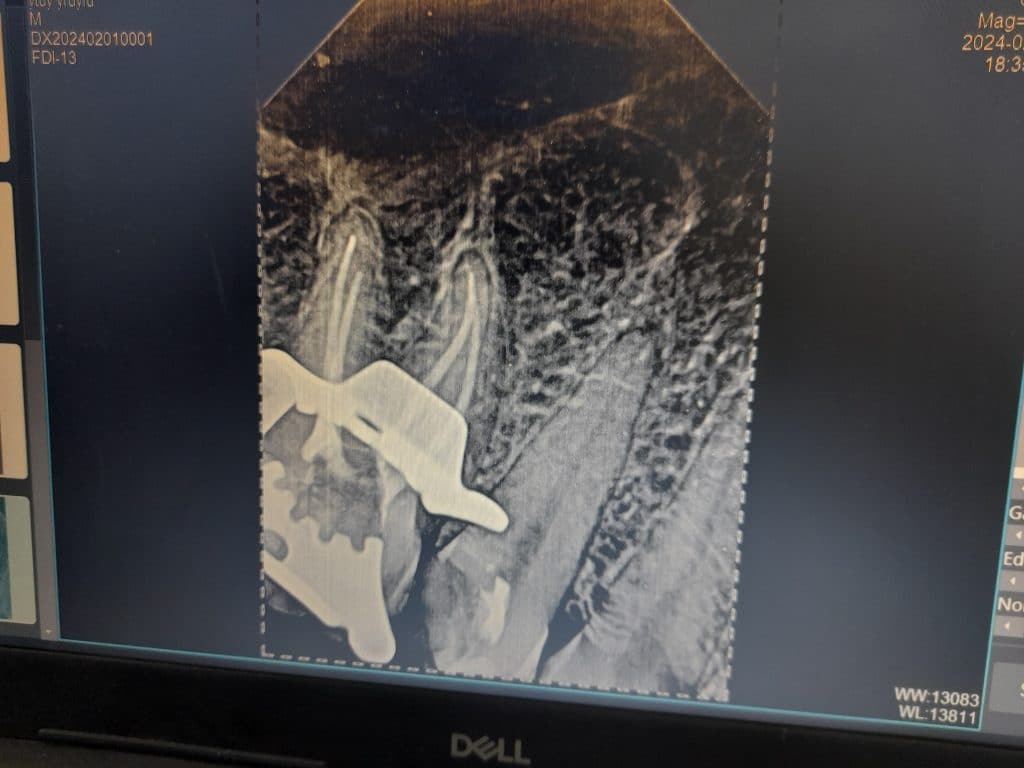

Tooth 36 diagnosis: necrotic pulp and acute apical periodontitis

Root canal treatment, lateral condensation obturation, resin based sealer. Tooth 36